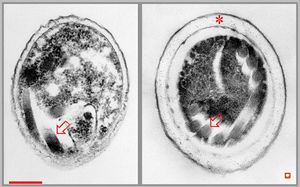

Nosema - brain, rabbit